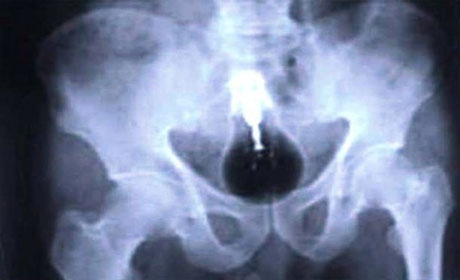

İnsan nələri udmağa qadir deyil? Yaxud mədədən nələr gəlib-keçmir? ANN.Az-in oxuculara təqdim etdiyi fotolar bir daha insanın nələrə qadir olduğunu göstərir. 1. İlan balığı2. Qaşıq3. Batareyalar4. Canlı qurbağa5. Mismar6. Dərmanlar 7. Nişan üzüyü8. Qayçı9. Tük yumağı10. Mobil telefom11. Qələm12. Yay13. Əl bombası14. Açar15. Lampa